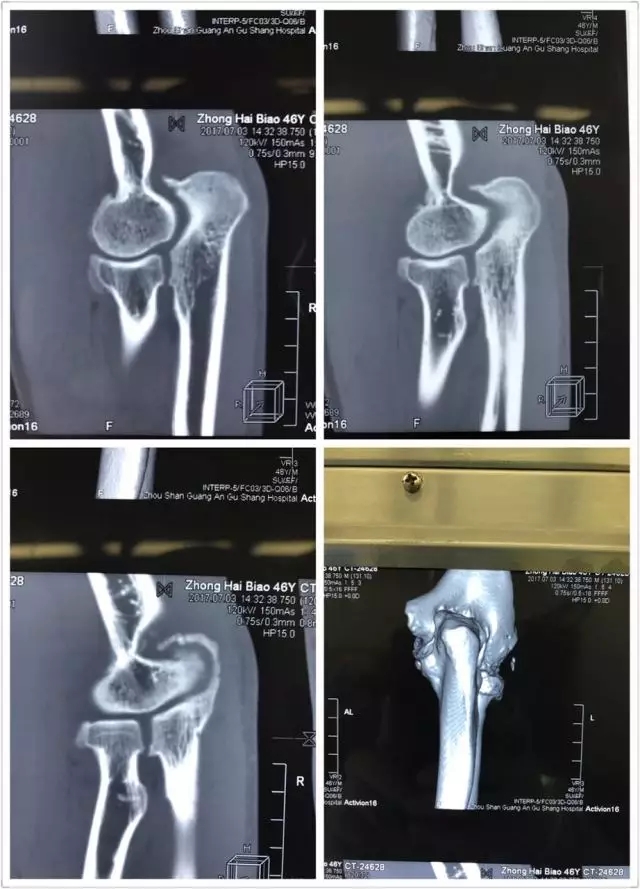

患者鐘某某,男,46歲,漁民,由于一年前的一次手肘部外傷,在受傷后一直隱隱作痛,加上日常生活中勞作過(guò)度,所以手臂一直處在“過(guò)勞”的狀態(tài)。

近幾個(gè)月,持續(xù)的疼痛讓這位輕易不言痛的大男人也忍無(wú)可忍,有時(shí)候某一個(gè)動(dòng)作所致,會(huì)疼得出汗,也有過(guò)很多個(gè)夜晚無(wú)法入眠的疼痛時(shí)刻。嘗試過(guò)各種止痛藥、膏藥,都無(wú)法根除疾病,并逐漸出現(xiàn)肘關(guān)節(jié)不能伸直。

于是他慕名來(lái)到舟山廣安醫(yī)院危立軍副院長(zhǎng)處就診,診斷為肘關(guān)節(jié)內(nèi)游離體,肘關(guān)節(jié)伸直功能障礙。

舟山廣安醫(yī)院關(guān)節(jié)鏡與運(yùn)動(dòng)醫(yī)學(xué)科羅軍主任帶領(lǐng)其王鵬醫(yī)師及團(tuán)隊(duì)成員采用國(guó)際上先進(jìn)的肘關(guān)節(jié)鏡技術(shù),為這位患者施行肘關(guān)節(jié)鏡下游離體取出,骨贅清除,尺骨鷹嘴窩成形術(shù),術(shù)后患者癥狀明顯好轉(zhuǎn),折磨了一年多的疼痛消失了,臉上重新露出了笑容。